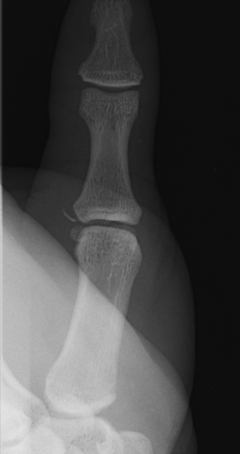

X-ray

3 types Bony avulsion

1. Small fragment pulled away from P1

2. Large intra-articular fracture involving >1/4 articular surface

3. S-H III in paediatric population